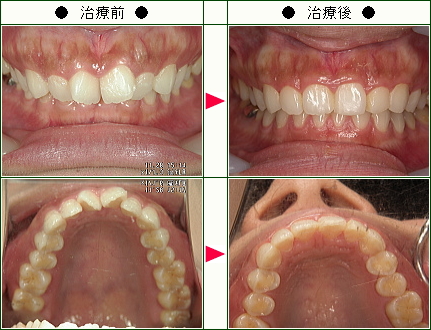

☆歯のデコボコ矯正症例(Y.U様 39歳 男性)

きっかけは以前から上前歯の歯並びが気になっていて、部分矯正が可能ということで。

治療期間は2月から9月の間7ヵ月。

困ったことはブリッジの装着感がなじむまでの違和感が嫌だったが、歯並びが改善している実感もあった。

マウスピースも、新しい型になるたびに装着した時にはきつさがあったが、2~3日で慣れてしまうのでそこまで困らなかった。

抜歯が必要なら、矯正までしなかったかも。(自分の歯並びがそこまで重度ではなかったと思うので)

担当していただいたスタッフの方は、とても感じが良くて安心して矯正をお願いできました。

自分の場合だけかもしれませんが、初めのカウンセリングから同じ方が担当して下さったこともあり、安心してみて頂けたのかと。(治療中もゴトゴトする事、伝えてくれることがリラックスしていられた細かい心配りなのかと思いました。)